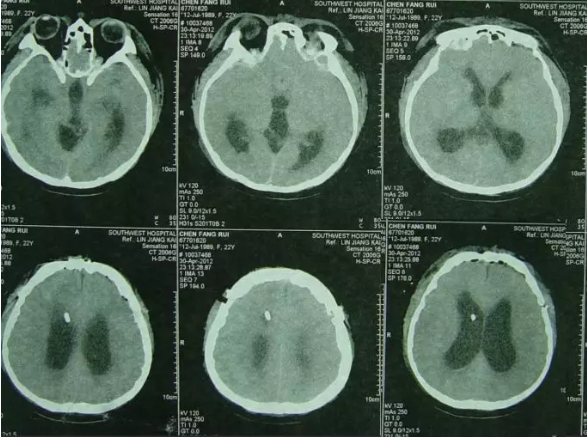

入院当天急诊进行了侧脑室外引流术+原外引流管拔除术,术后复查头颅CT:脑室外引流管位置良好(图-8)。

图-8:2012年5月10日头CT

住院治疗第8天即2012年5月18日,入院时意识嗜睡好转为意识清楚;体温好转为正常;双下肢无力抬不起好转为腿部有劲可以抬起,但反应慢;大小便失禁、尿崩症明显减轻;间断呕吐消失;查头CT:脑室缩小(图-9)。

图-9:2012年5月18日头CT

住院治疗第103天后即2012年8月20日,由搀扶下走路好转为独立起床、行走正常。脑脊液各项检查指标均正常后,住院治疗第106天后即2012年8月23日进行了脑室腹腔分流术,术后当天复查头颅CT:脑室分流管位置良好(图-11)。

图-11:2012年8月23日头CT